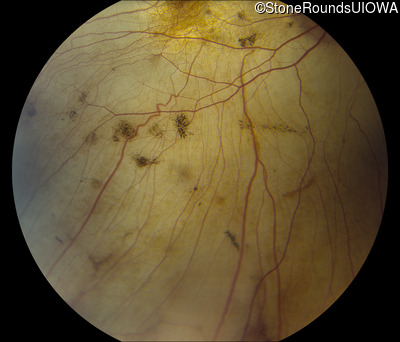

Fundus Photography - Left - 20/25 -2

Exemplar